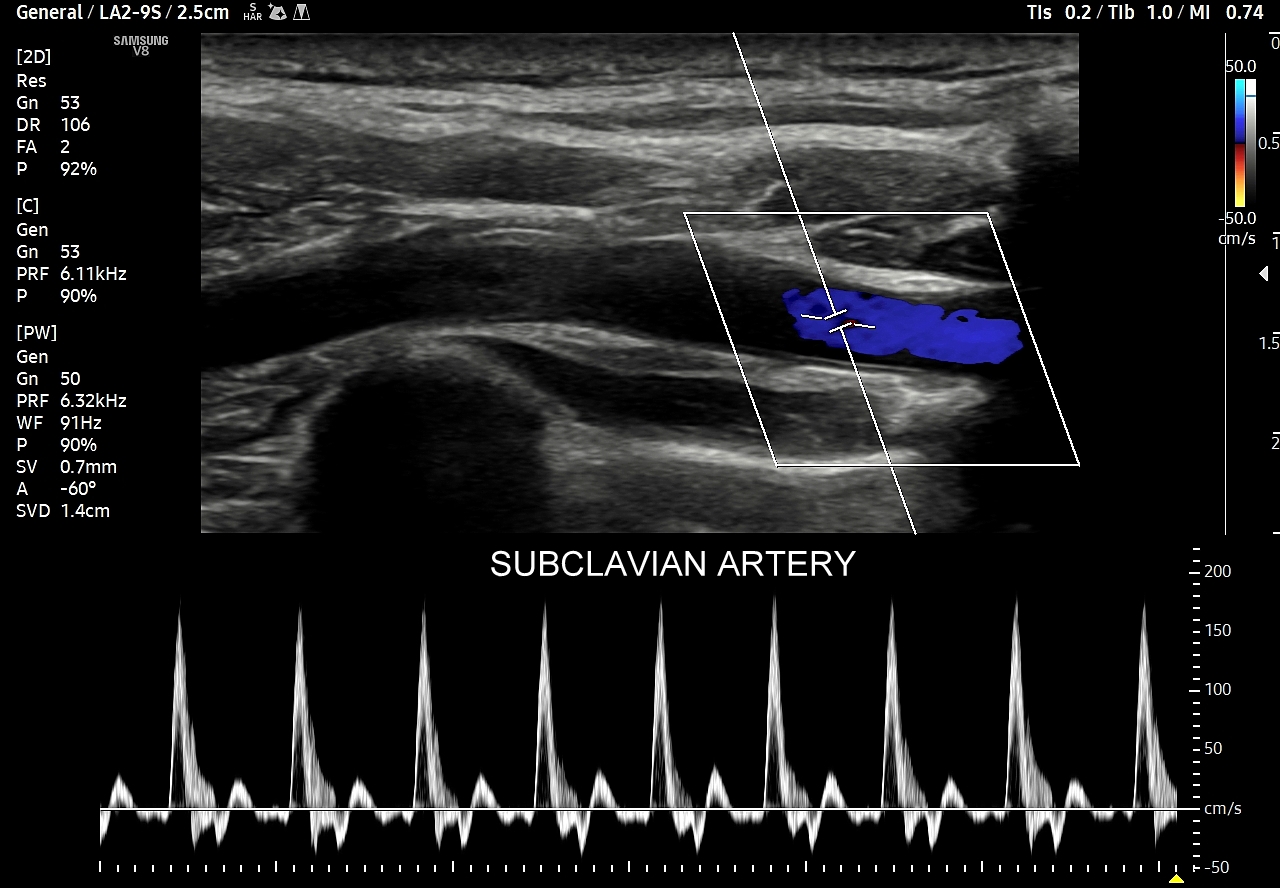

- Z kolei profile o wysokiej pulsacyjności charakteryzują się tym, iż posiadają wąskie i ostre piki skurczowe, a w fazie rozkurczowej odwrócone lub/i nieobecne przepływy. Profile tego typu występują w tętnicach unaczyniających kończyny.

Podsumowując, przepływ krwi w konkretnych tętnicach, w tym jego przyspieszenie i prędkość, wynikają z 1/ charakteru pracy pompy, tj. serca; 2/ stanu naczyń per se, tj. elastyczności i drożności; oraz z 3/ właściwości biologicznych unaczynionego narządu. W związku z powyższym prawidłowy profil przepływu we wszystkich rodzajach tętnic w krążeniu dużym w warunkach fizjologicznych, tj. przy zdrowym sercu, zdrowych naczyniach i zdrowym docelowym narządzie, zawsze cechuje się szybkim narastaniem prędkości przepływu, czyli stromym ramieniem wstępującym; krótkim czasem akceleracji (ang. acceleration time) od początku tegoż ramienia do pierwszego załamania na nim, tj. zasadniczo nie przekracza 70 ms, a zwykle oscyluje wokół 30 ms. Poza tym w przypadku młodych i elastycznych tętnic podążających do kończyn, tj. naczyń z przepływem wysokooporowym, w fazie rozkurczowej przepływu obserwuje się wyższe załamki i często więcej załamków (zamiast jednego nawet do trzech). W krążeniu płucnym czas akceleracji prawidłowo przekracza 100 ms.

W przypadku tętnic podążających do kończyn w warunkach spoczynkowych obserwuje się charakterystyczne wielozałamkowe profile przepływów zawierające od 2 do nawet 4 następujących po sobie przeciwstawnych załamków o zmniejszającej się amplitudzie, przy czym w tętnicach tych zwykle nie obserwuje się ciągłego przepływu w fazie rozkurczowej. Stały lub prawie stały przepływ rozkurczowy, tj. przepływ o pośredniej pulsacyjności, może pojawić się w tętnicach kończyn w trakcie intensywnego wysiłku fizycznego.